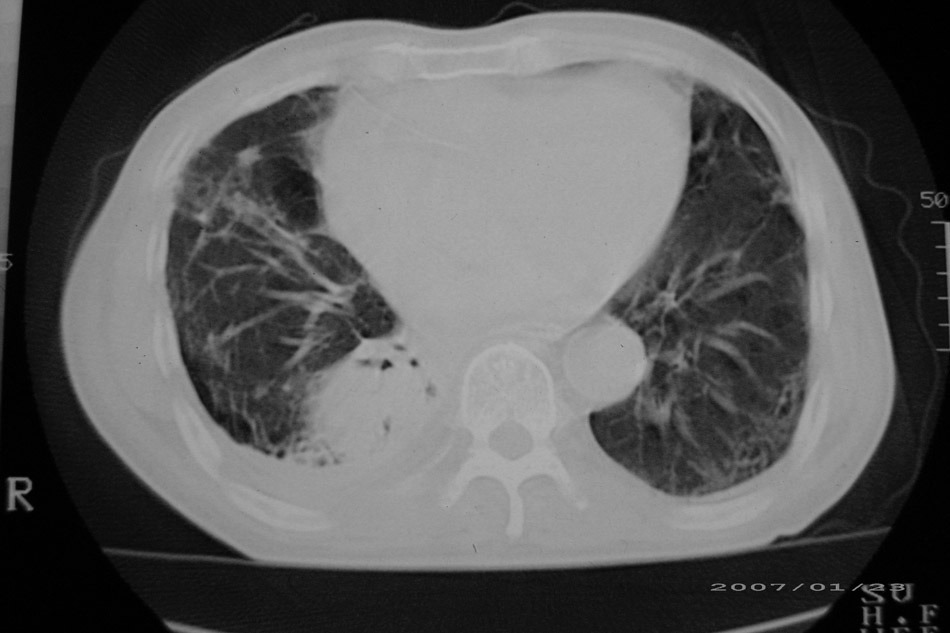

以下是引用天南地北在2007-1-24 18:00:00的发言:[br]1:右下肺内基底段类椭圆性肿快影:考虑1:右下球形肺炎2:右下肺隔离症,建议抗炎治疗后复查。[br]2:右肺及左下肺感染,右侧少量胸腔积液。

以下是引用hhcckk在2007-1-24 18:11:00的发言:[br]病灶周围胸膜反应比较明显,考虑炎症可能性大点,病人年龄较大,病灶成块状,肿瘤也不能排除,可可西里老师看片子的确很仔细,隔离肺暂时我觉得证据的说服力不大,上下层面显示条状影范围较长,可能是增厚的胸膜,可以做个增强鉴别一下